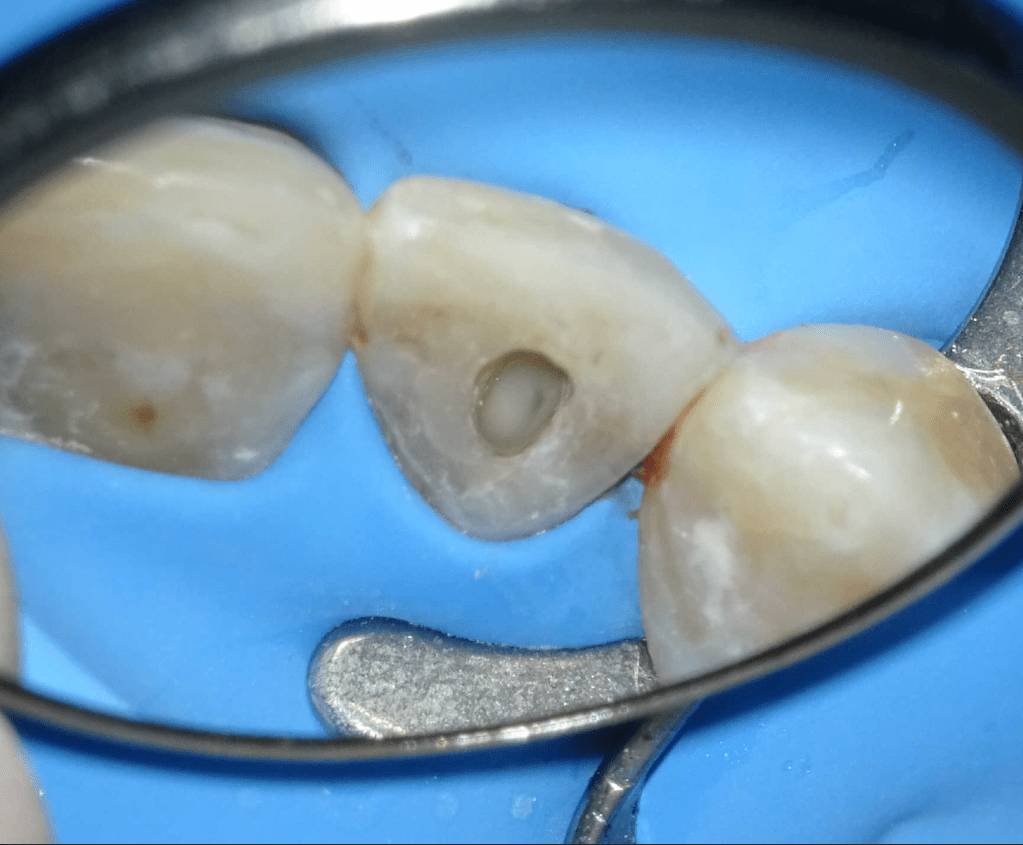

Pulpotomía biodentine + reco preendio